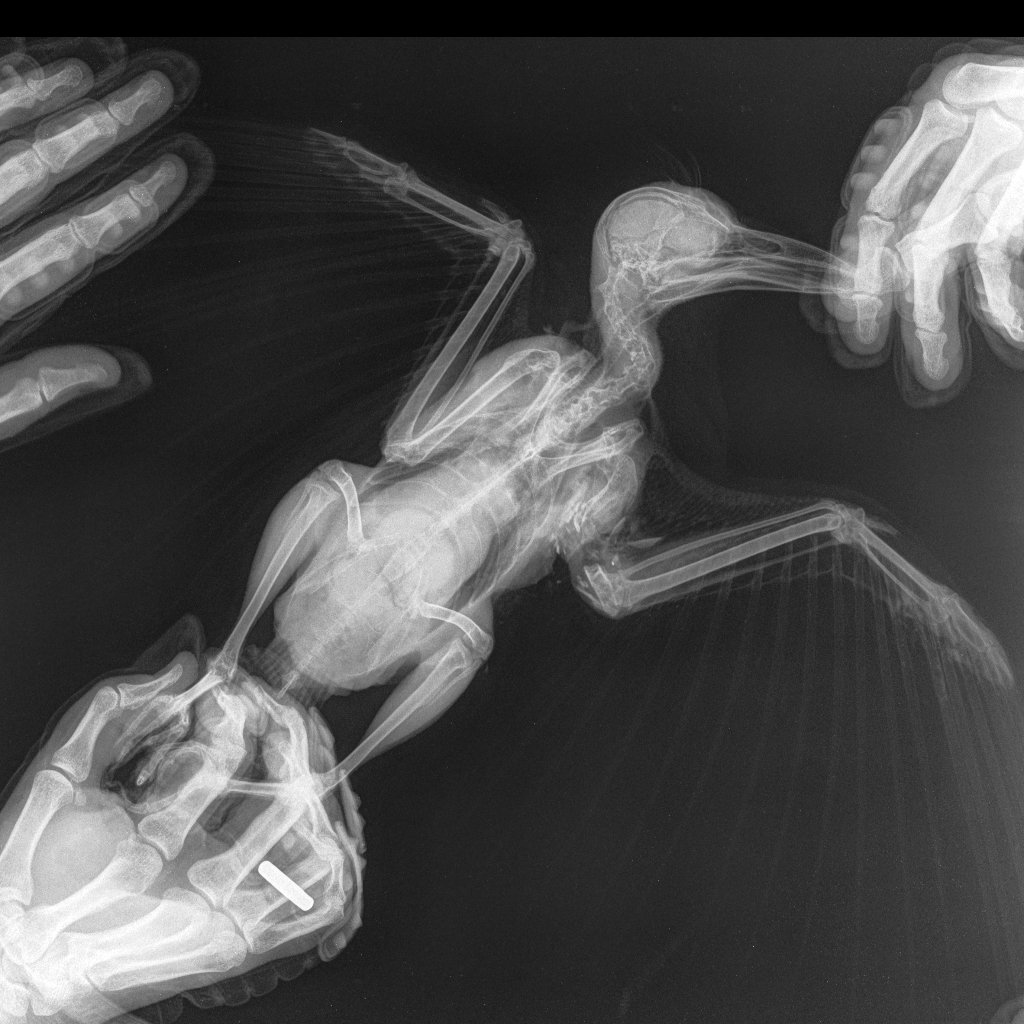

1098503161__10kg--..LAT-26_03.2022-19_59_17-686.thumb.JPEG.0b0de00b517fe909432f66d4f680fa5c.JPEG184647199__10kg--..LAT-26_03.2022-19_59_18-451.thumb.JPEG.3d577b4228d08d7e23a8b5ccfa286c8b.JPEG

Плечевая кость вся раздробленна. Не знаю что делать, операция по удалению или ампутации крыла довольно накладно стоит.

Крыло так то сильное, мышцы работают, но по снимку даже плечо просело вниз. Внутри видимо воспаление, кусочки везде разбросаны.

По снимку целы